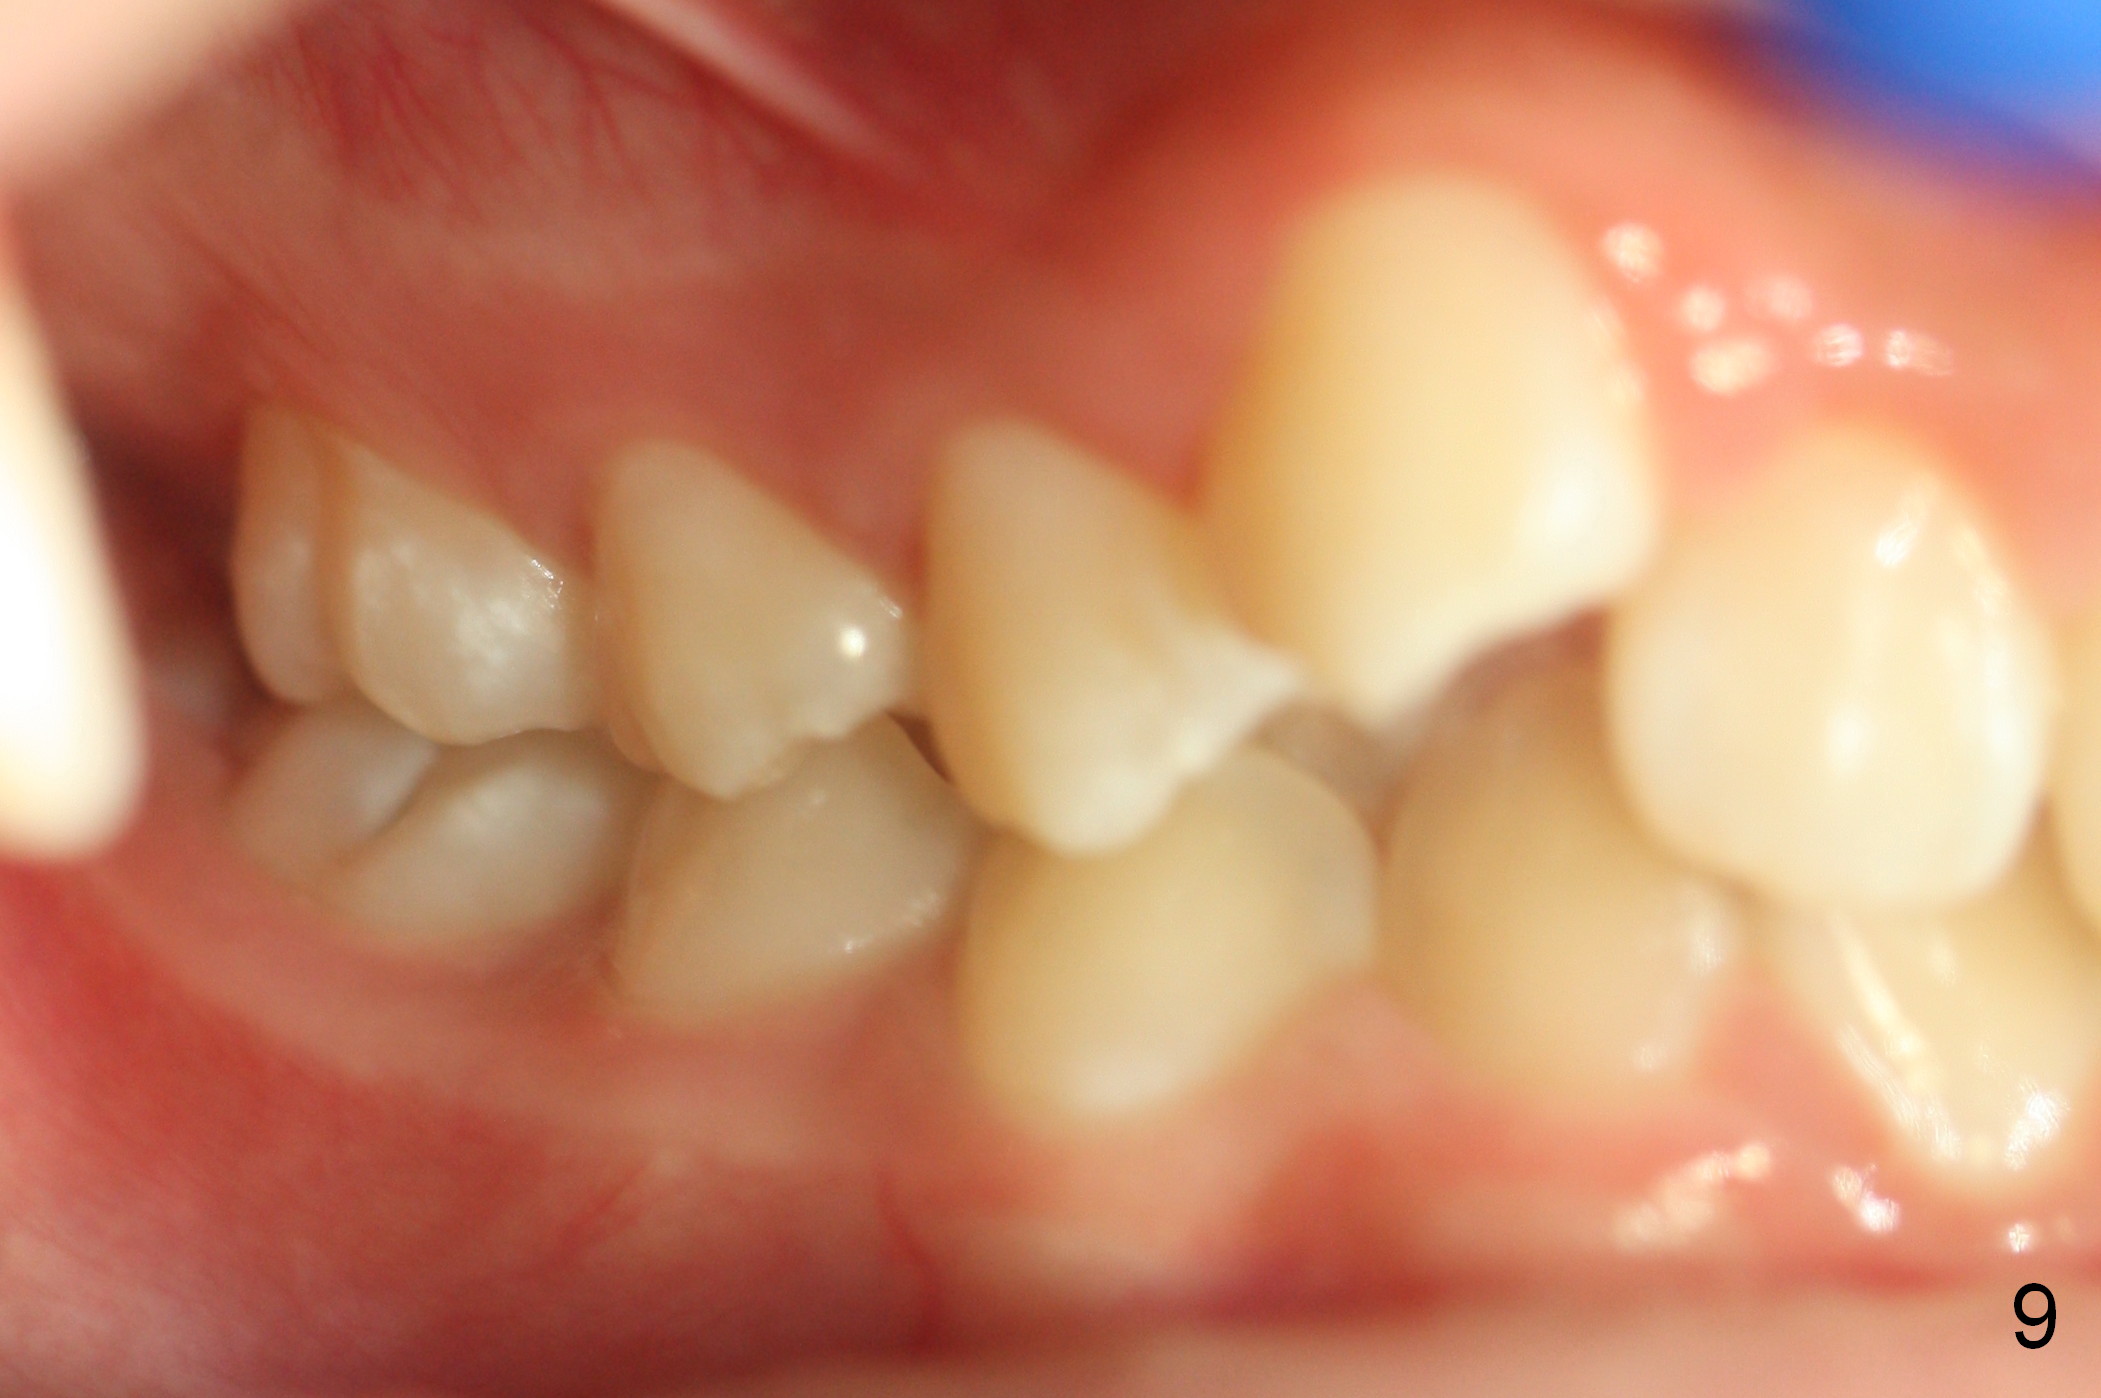

A 13-year-old girl presents for orthodontic consultation.  Chief complaint is crooked teeth.  Her brother is finishing 4 extraction ortho.

Looking at the records, the lower incisors are protrusive and have crowding, so think extraction.  There is enough combined crowding and class II to warrant extraction.  Since there is lower crowding, it would be 4 bicuspid extractions with the sliding mechanics using elastics or Niti closing coil springs. Closing the extraction space by maintaining the lower incisor position and moving the lower molars forward.  The upper arch is 50/50 front going back/back coming forward. Dr. Doug Ness, March 13, 2015 1:18 AM